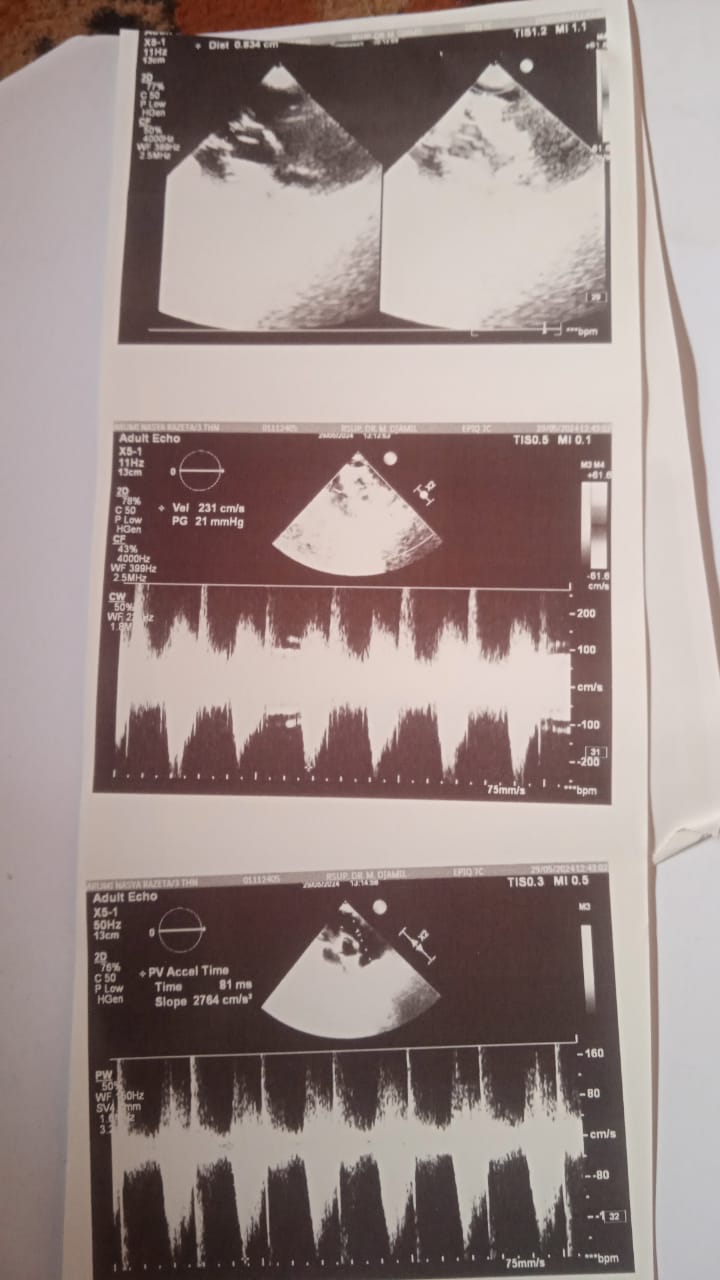

Tidurnya juga terganggu karena sesak napas yang disebabkan oleh flu dan batuk, yang membuat sesaknya semakin parah. Dari hasil pemeriksaan jantung Arumi bulan lalu, dokter sangat menyarankan agar Arumi menjalani operasi.

Insyaallah bulan depan ini Arumi akan dirujuk kembali ke RSUP. Dr. M. Djamil Padang untuk menjalani pemeriksaan echo jantung dan semoga hasilnya bagus.

Kabar Arumi sekarang masih batuk dan semakin sesak serta dari hasil pemeriksaan echo, jantungnya semakin memburuk dimana bocornya semakin besar.

Dokter jantung menyarankan agar Arumi segera dirujuk ke RS Harapan Kita di Jakarta, karena kalau di RS Padang belum bisa dilakukan operasi jantung. Sebab harus menunggu, supaya berat badannya menjadi 18 kilogram dulu.